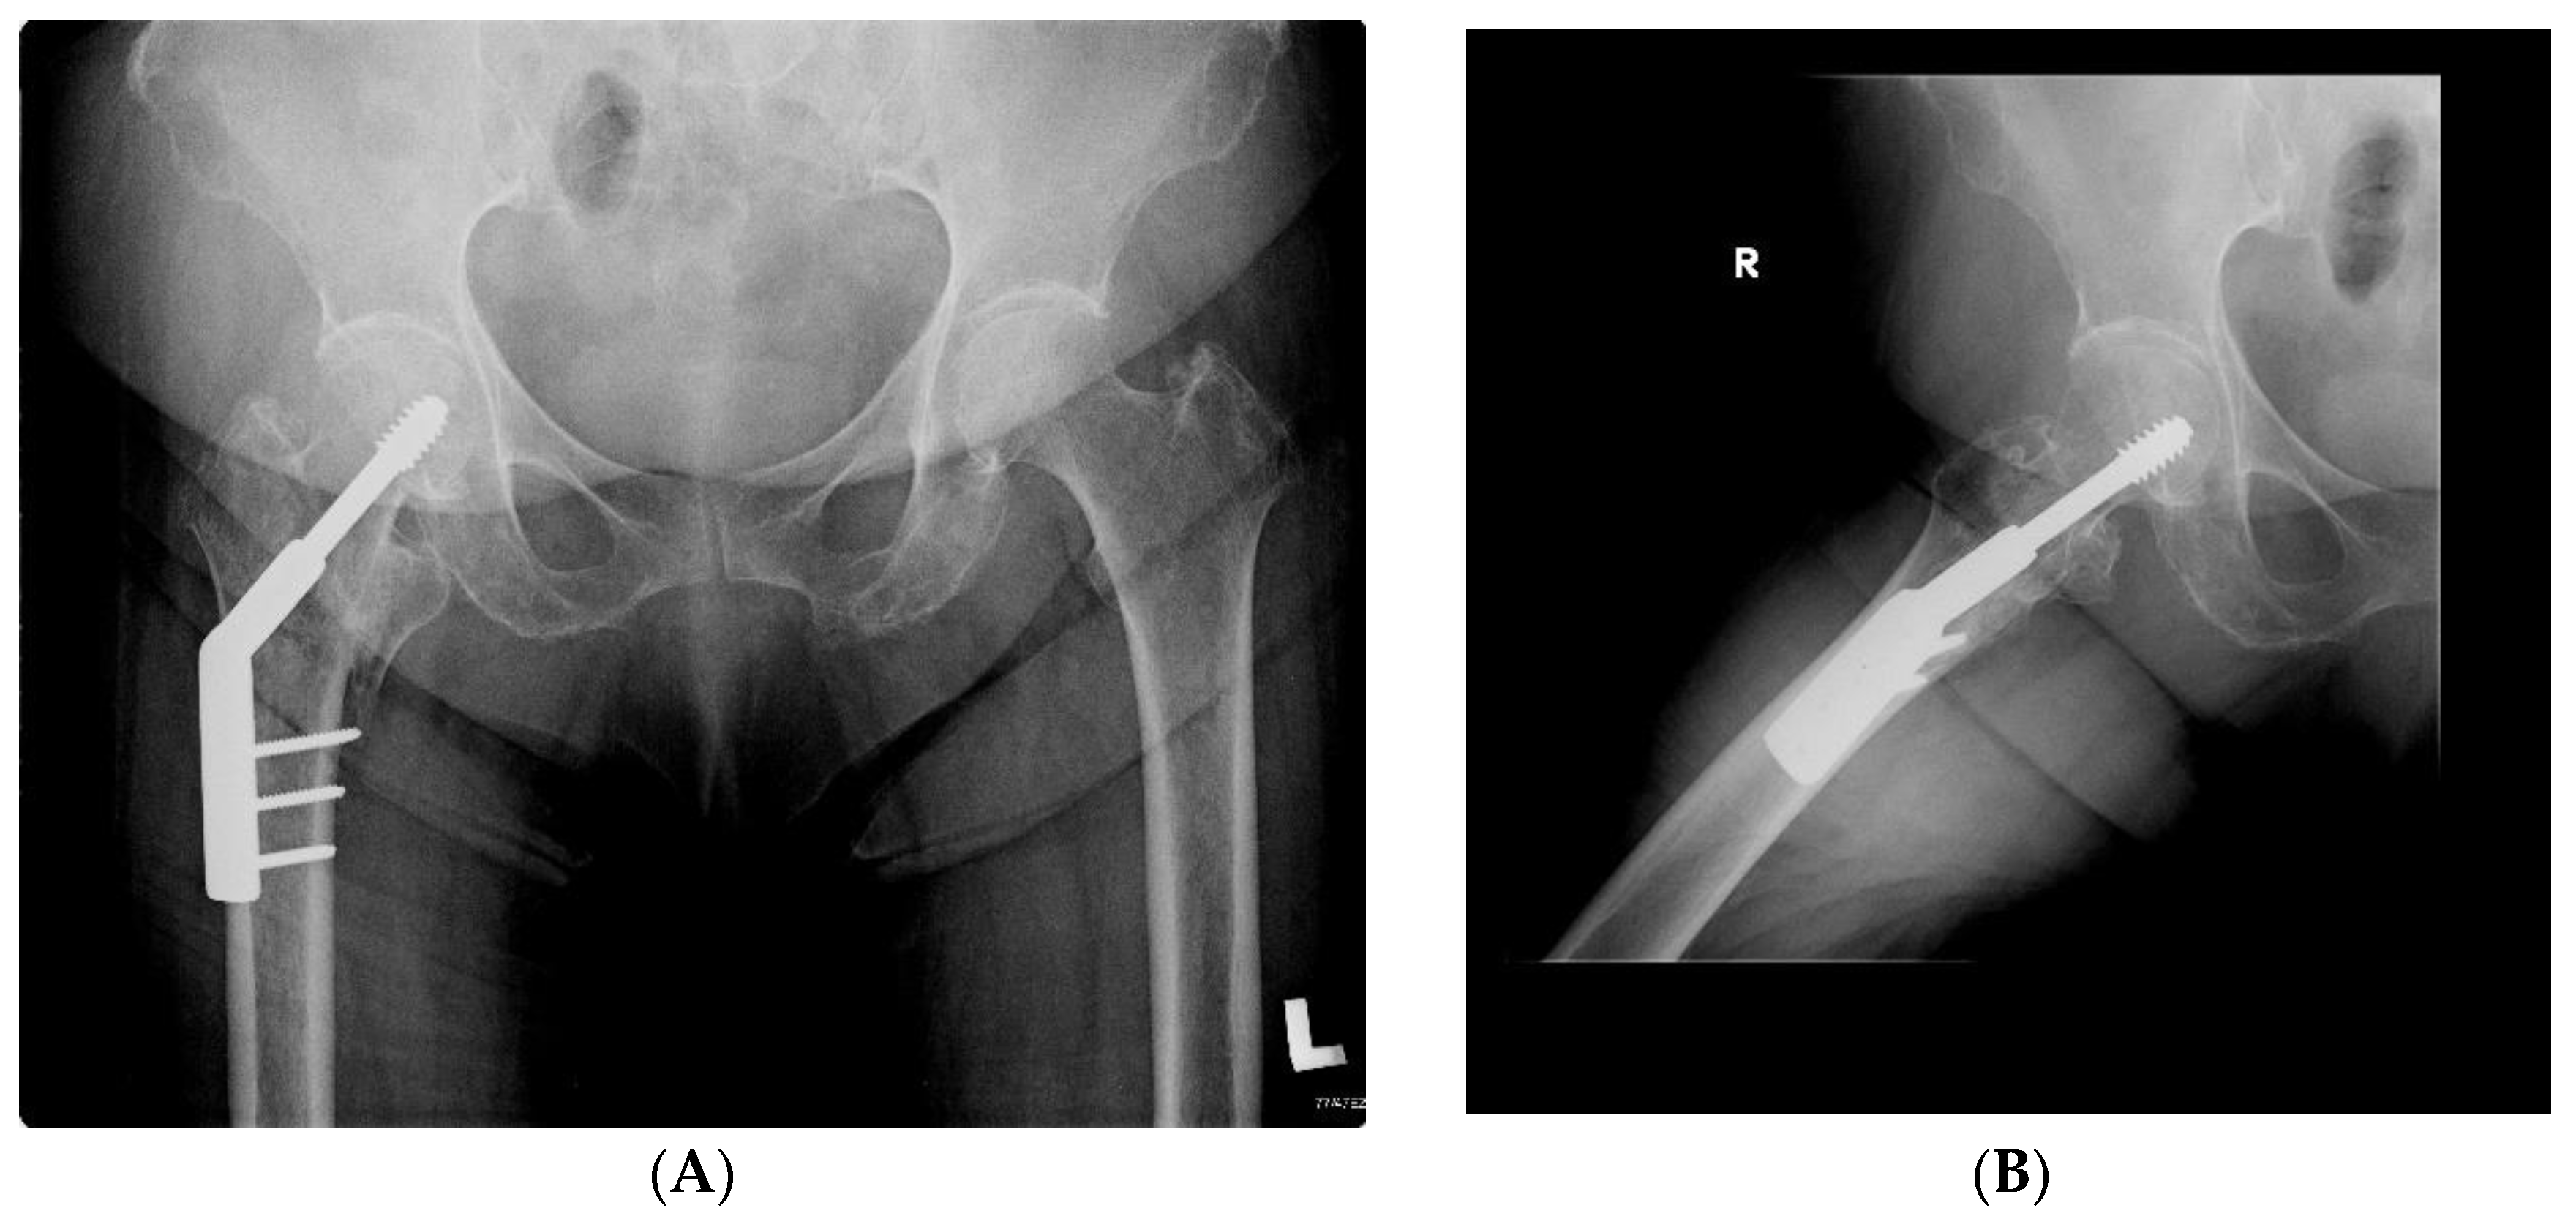

2.6. Radiographic Analysis

- symmetry of the neck-shaft angle (NSA)—operated femur and its opposite side (assessment for the presence of valgus or varus position);

- symmetry of the position of the neck screw in relation to the axis of the femoral neck (screw located on the axis or below the axis vs. located above the axis);

- the axis of the intramedullary nail in relation to the axis of the femur (evaluated in the anterior–posterior view: varus position—the distal part of the nail resting on the medial cortex; axial position—the axis of the nail coincides with the axis of the femoral shaft; valgus position—the distal part of the nail resting on the cortex layer of the femur on the lateral side);

- the minimum distance between the tip of the neck screw and the articular surface of the femoral head (arithmetic mean of the distance measured in the anterior–posterior and axial projection);

- symmetry of the length of the operated limb (the difference in the height of the lesser trochanter position) shortening by >1 cm.

3.4. Symmetry/Assymetry in Radiographic Analysis

- DHS group: in 33 patients, the screw was located on the axis or below; in three patients, the screw was located above the axis,

- Gamma group: in 38 patients, the screw was located on the axis or below; in four patients, the screw was located above the axis.